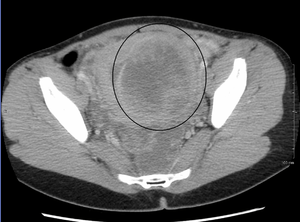

While palpation used in a pelvic examination can typically identify the presence of larger fibroids, gynecologic ultrasonography (ultrasound) has evolved as the standard tool to evaluate the uterus for fibroids. Sonography will depict the fibroids as focal masses with a heterogeneous texture, which usually cause shadowing of the ultrasound beam. The location can be determined and dimensions of the lesion measured. Also magnetic resonance imaging (MRI) can be used to define the depiction of the size and location of the fibroids within the uterus.

Imaging modalities cannot clearly distinguish between the benign uterine leiomyoma and the malignant uterine leiomyosarcoma, however, the latter is quite rare. Fast growth or unexpected growth, such as enlargement of a lesion after menopause, raise the level of suspicion that the lesion might be a sarcoma. Also, with advanced malignant lesions there may be evidence of local invasion. Biopsy is rarely performed and if performed, is rarely diagnostic. Should there be an uncertain diagnosis after ultrasounds and MRI imaging, surgery is generally indicated.

A very large (9 cm) fibroid of the uterus which is causing pelvic congestion syndrome as seen on CT